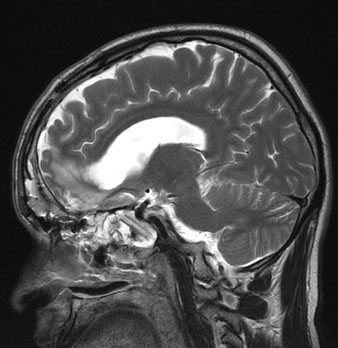

وأوضح الدكتور ماجد قلادة استشاري جراحة العمود الفقري والمخ والأعصاب، أن المريض تم تحويله من مستشفى آخر بعد محاولة علاجه بإجراء عمليتين ولكن دون جدوى. مشيرًا إلى أنه تم إخضاع المريض للفحوصات المخبرية والرنين المغناطيسي (M.R.I) والتصوير المقطعي (C.T. Scan) التي حددت بدقة أماكن الكسور المتهشمة.

وعن كيفية إصلاح كسور الجمجمة، أوضح الدكتور قلادة أنه بعد دراسة الملف الصحي للمريض تم وضع برنامج علاجي للمريض على مرحلتين، مشيرًا لى أن المرحلة الأولى شهدت إجراء عملية جراحية استغرقت 7 ساعات، تم فيها فتح الجمجمة من أعلى والاستعانة بجزء صغير من عضلة المضغ بالفم لإصلاح الغطاء الخارجي للمخ ومعالجة الكسور.